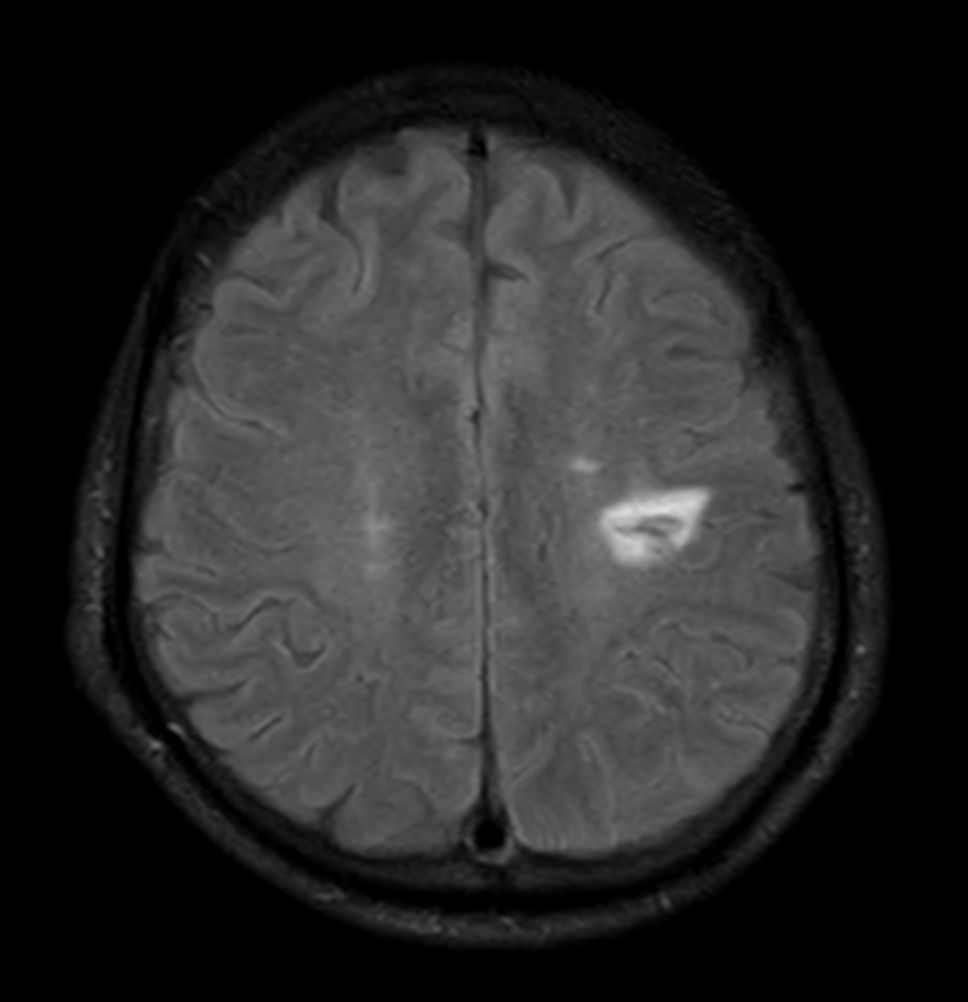

Brain small infarction

Patient with a small brain infarction. Compressed SENSE acceleration is used to speed up sequences while maintaining equal image quality. Three different diffusion methods are included; A fast 52 secs DWI EPI sequence, a high resolution DWI EPI sequence and a TSE based DWI sequence. A SWIp sequence is included offering high resolution 3D susceptibility weighted imaging to enhance contrast for deoxygenated (venous) blood or calcium deposits. 3D APT sequence is included providing contrast-free brain imaging, addressing the need for more confident diagnosis in brain neuro oncology by using the presence of endogenous cellular proteins to produce an MR signal. And a large FOV TOF MR Angiography sequence is included to check on brain vascular anatomy.

Axial T2w FLAIR - Compressed SENSE